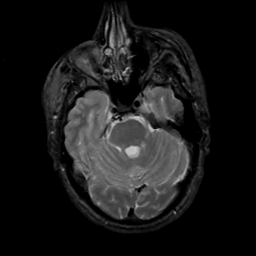

MR Study #5, March 10, 1991 -- Slice #16